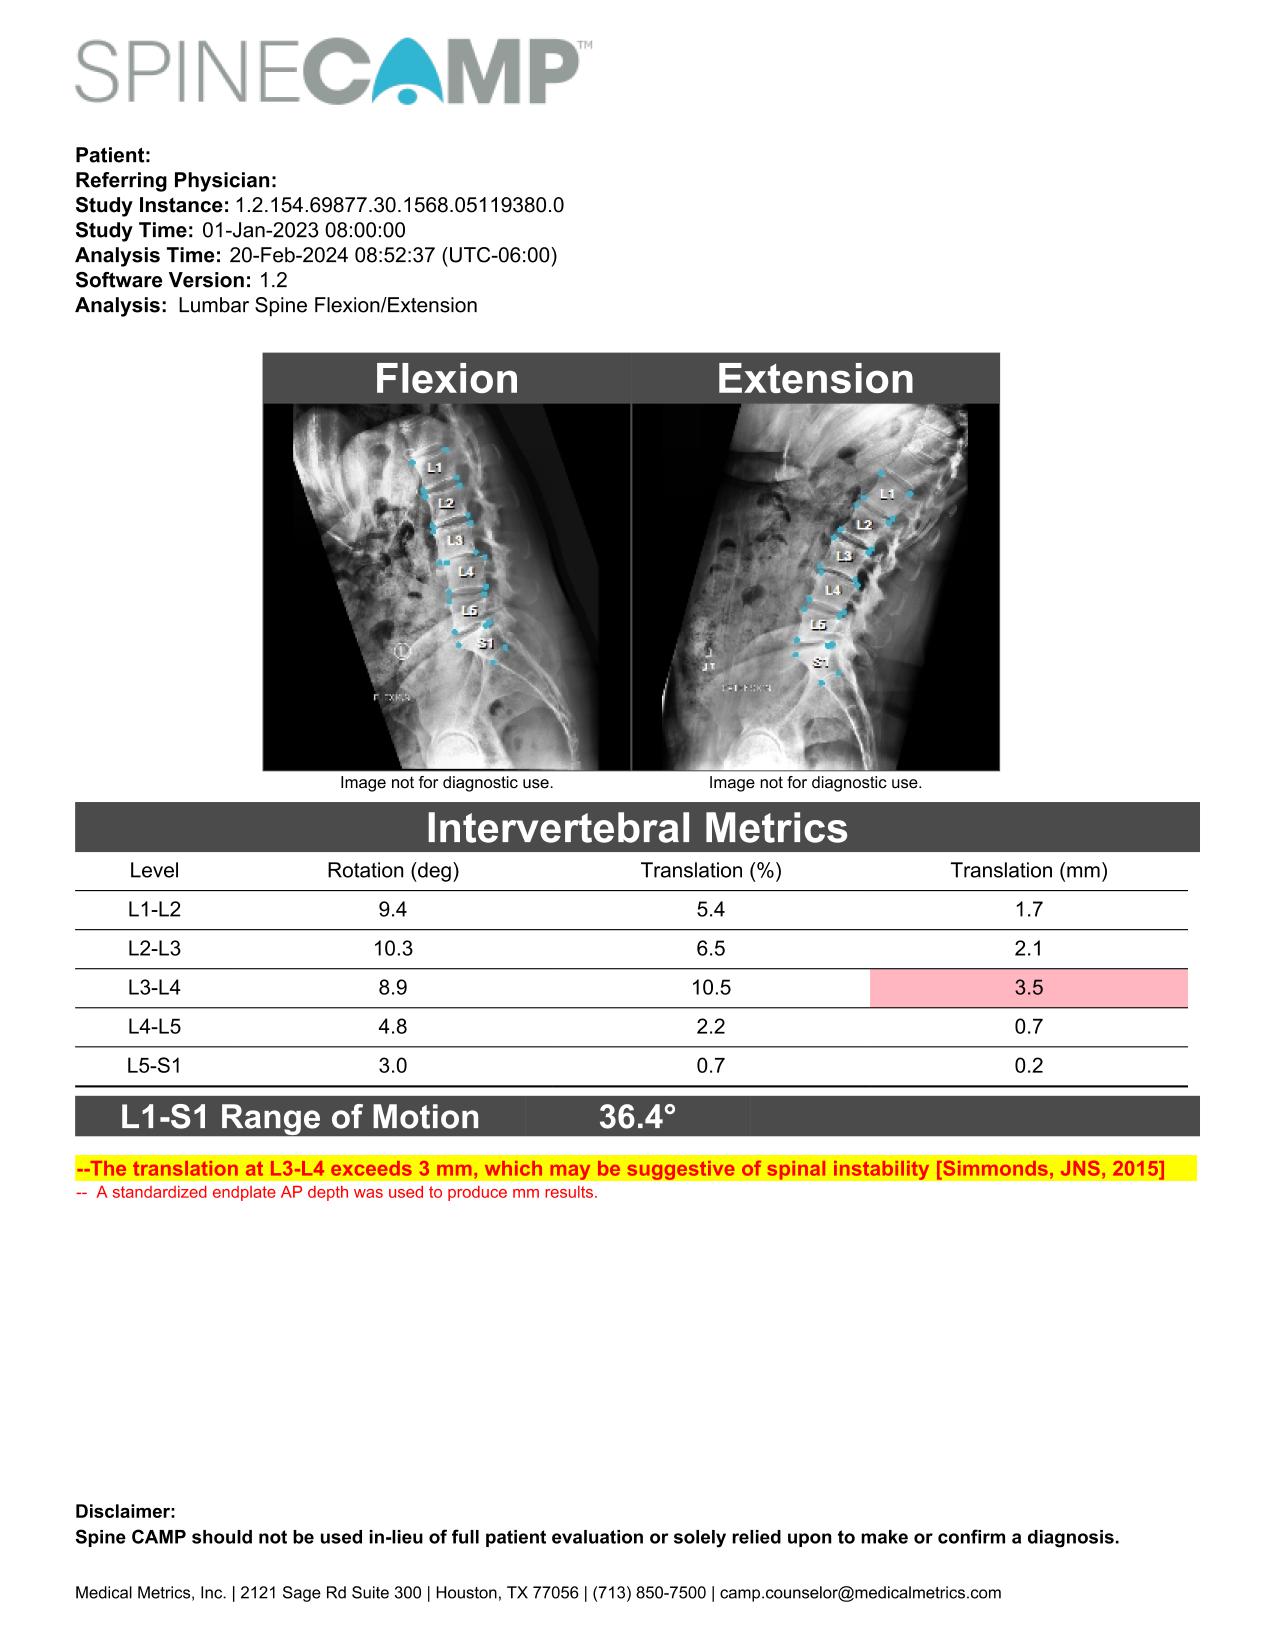

"We are excited to connect with clinical professionals and colleagues from the spinal device industry at the Spine Summit, and to demonstrate our imaging informatics capabilities" said Dennis Farrell, VP Medical Device Commercialization at MMI. "We look forward to sharing how the precision metrics provided by SpineCAMP can aid in objective assessment of spinal instability, alignment, fusion, motion preservation, and implant performance. Initial feedback from early adopting sites has been very positive, and we are thrilled by the reception.”

Introduction to SpineCAMP